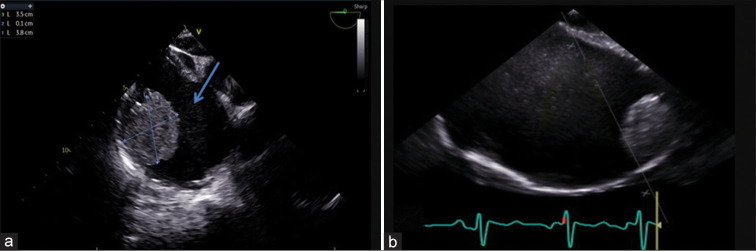

Cardiac masses are a significant cause of patient morbidity and mortality by virtue of their symptoms and surgical removal. Preoperative diagnosis of a cardiac mass is usually based on clinical correlation and transthoracic echocardiography findings. Myxomas are the most common benign cardiac tumors, commonly occurring in the left atrium attached to the interatrial septum near the fossa ovalis. Although, at times atypical location and unusual morphology may pose a diagnostic dilemma with 2D echocardiography. 3D echocardiography with its multifaceted advantages, including multiplanar cropping abilities and superior imaging quality can help distinguish between a clot and a myxoma.